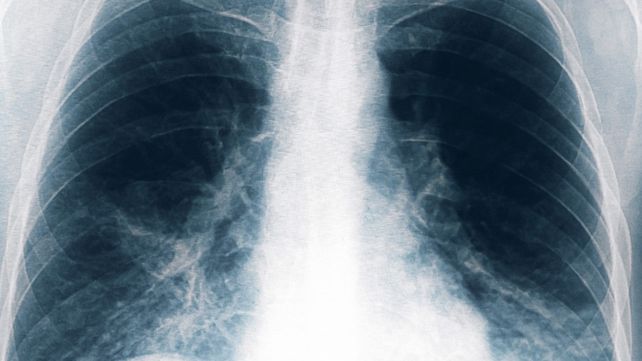

Neumonía bilateral por legionella: nuevos casos en Tucumán

Neumonía bilateral por legionella: crecen los casos en Tucumán. Hay ocho nuevos casos y son seis los decesos.

Otras ocho personas resultaron afectadas por el brote de neumonía bilateral causado por la bacteria legionella pneumophilia, una de ellas en estado grave, tras un cambio en el criterio de selección de los pacientes, con lo que suman 13 casos en total y seis fallecidos, informó el ministro de Salud de Tucumán, Luis Medina Ruiz.